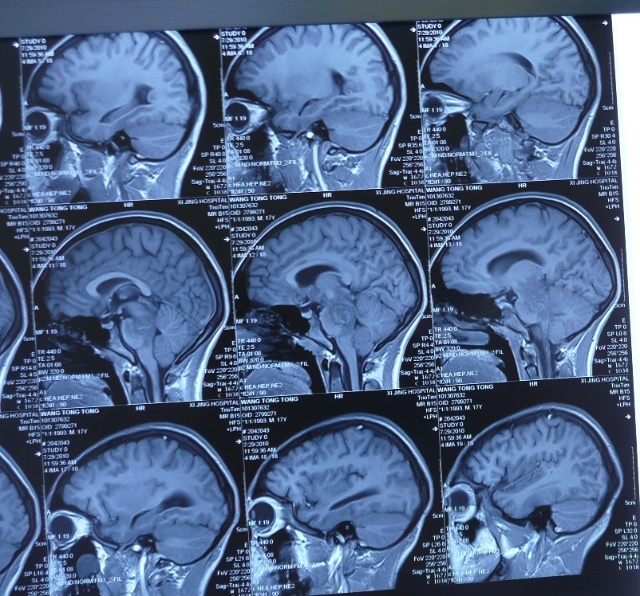

799286 脑干占位

图片尺寸919x1149